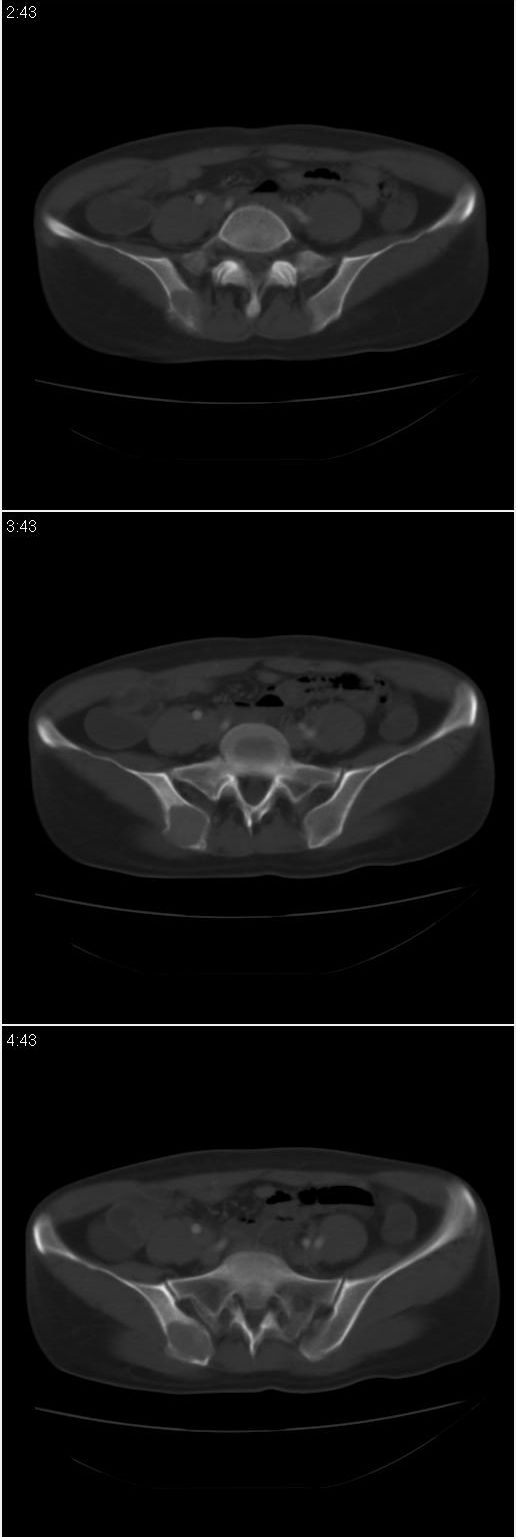

标题: CT13002:女,46岁。有子宫肌瘤手术史,现在出现右臀部向腿 [打印本页]

标题: CT13002:女,46岁。有子宫肌瘤手术史,现在出现右臀部向腿

考虑右侧髂骨动脉瘤样骨囊肿。

右侧髂骨动脉瘤样骨囊肿

骨囊肿

考虑1、骨囊肿;2、骨巨细胞瘤。

考虑: 右侧髂骨动脉瘤样骨囊肿可能性大.

考虑右侧髂骨动脉瘤样骨囊肿

考虑 巨细胞瘤。其他待排

病变内部无分隔,未见骨嵴,边缘无硬化考虑动脉瘤样骨囊肿。

1,如果是转移瘤,必须有一定的病史,转移瘤以溶骨性骨破坏无膨胀性骨改变.2,如果是骨囊肿的话,病变的边缘要光整,此病例不是那么光整.3,如果是骨巨的话,好发年龄20-40岁,髂骨也是骨巨的好发部位,同时骨端是骨巨的好发特点,这个病例恰好发生在髂骨耳状面边缘,呈膨胀性生长,虽说年龄偏大了些,但本人还是倾向于骨巨的诊断

考虑:右侧髂骨动脉瘤样骨囊肿,巨细胞瘤待排。

考虑右侧髂骨骨囊肿可能性大。盆腔左侧可见混杂密度区,请告知手术方式,充盈肠管重扫除外占位性病变.

骨巨细胞瘤。鉴别,1,骨囊肿;好发于长骨的干骺端,多见于青少年,骨盆骨囊肿特点是,病变内可有不规则骨小梁间隔,呈肥皂泡状/蜂窝状,骨囊肿周围有硬化边,无骨质破坏及骨膜反映,无软组织肿块。2,动脉瘤样骨囊肿;液平及薄层密质硬化边。3,骨慢性感染;多有疼痛,发热病史,病变周围模糊,可有明显的骨质增生。

右髂骨见一类圆形略高密度区,似见分层,骨质破坏不明显

考虑良性病变,以动脉瘤样骨囊肿可能性大

考虑为:右侧髂骨良性骨肿瘤或骨肿瘤样病变(动脉瘤样骨囊肿?骨巨细胞瘤?)。

右侧髂骨后缘囊状膨胀性骨质改变,无明显骨间隔,周围无明显硬化及骨膜反应,周围软组织无异常,相邻骨组织密度增高,考虑:动脉瘤样骨囊肿可能,要注意与骨巨细胞瘤及转移瘤鉴别。

囊性;密度均;未见分格;骨囊肿

右侧髂骨膨胀性骨质破坏区 囊内密度尚均匀 骨巨细胞瘤可能性大 动脉瘤样骨囊肿不除外 建议mr观察囊内成分明确诊断 左侧附件区包裹性积液

右侧髂后上棘局限性囊状骨质破坏,大部分界清,似见轻度硬化边,内无分格及钙化,病灶上部局部显示模糊。考虑;骨巨细胞瘤可能大,不除外abc。另可见子宫肌瘤术后子宫缺如。

临床和影像学表现:女性患者46岁,有子宫肌瘤手术病史。影像所见可见残余宫颈部分,左右附件未见新生物;右髂骨翼后端囊状膨胀性骨破坏,囊性部分感觉有强化(楼主标上增强前后的ct值就很好了),未见明确的液—液平面,周边硬化不明显或轻度硬化。

分析:患者年龄46岁,没有明确外伤病史,病变呈膨胀性骨破坏,囊性部分未见明确的液—液平面,周边硬化不明显。综合分析该病例比较符合骨巨细胞瘤,不太符合动脉瘤样骨囊肿。

诊断:1、首先考虑骨巨细胞瘤;2子宫肌瘤术后改变